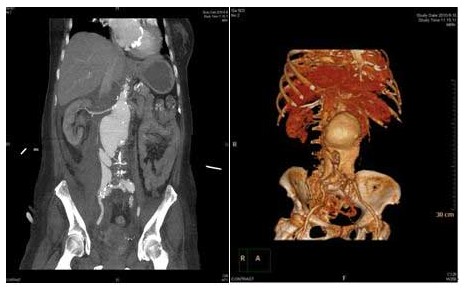

血甲疝外科成功抢救一例罕见肾上型腹主动脉瘤破裂病人

肾上型腹主动脉瘤影像影像